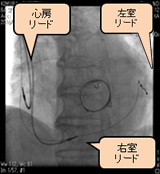

3.心臓再同期療法(CRT)とは?

CRTの大きな目的は、左右から心室をペーシングし、心臓のポンプ機能を改善させることです。心臓内の収縮のタイミングのズレを左右からのペーシングにより補正することで、正常に近いポンプ機能をとり戻す治療法です。ICDと同様に、本体、リードの植込み手術が必要となります。大きな違いはありませんが、右房、右室のほかに、心臓の左右の収縮するタイミングのズレを補正するペーシングを行うために、冠状静脈内を通して左室側壁へもリードが留置されます。(図6)